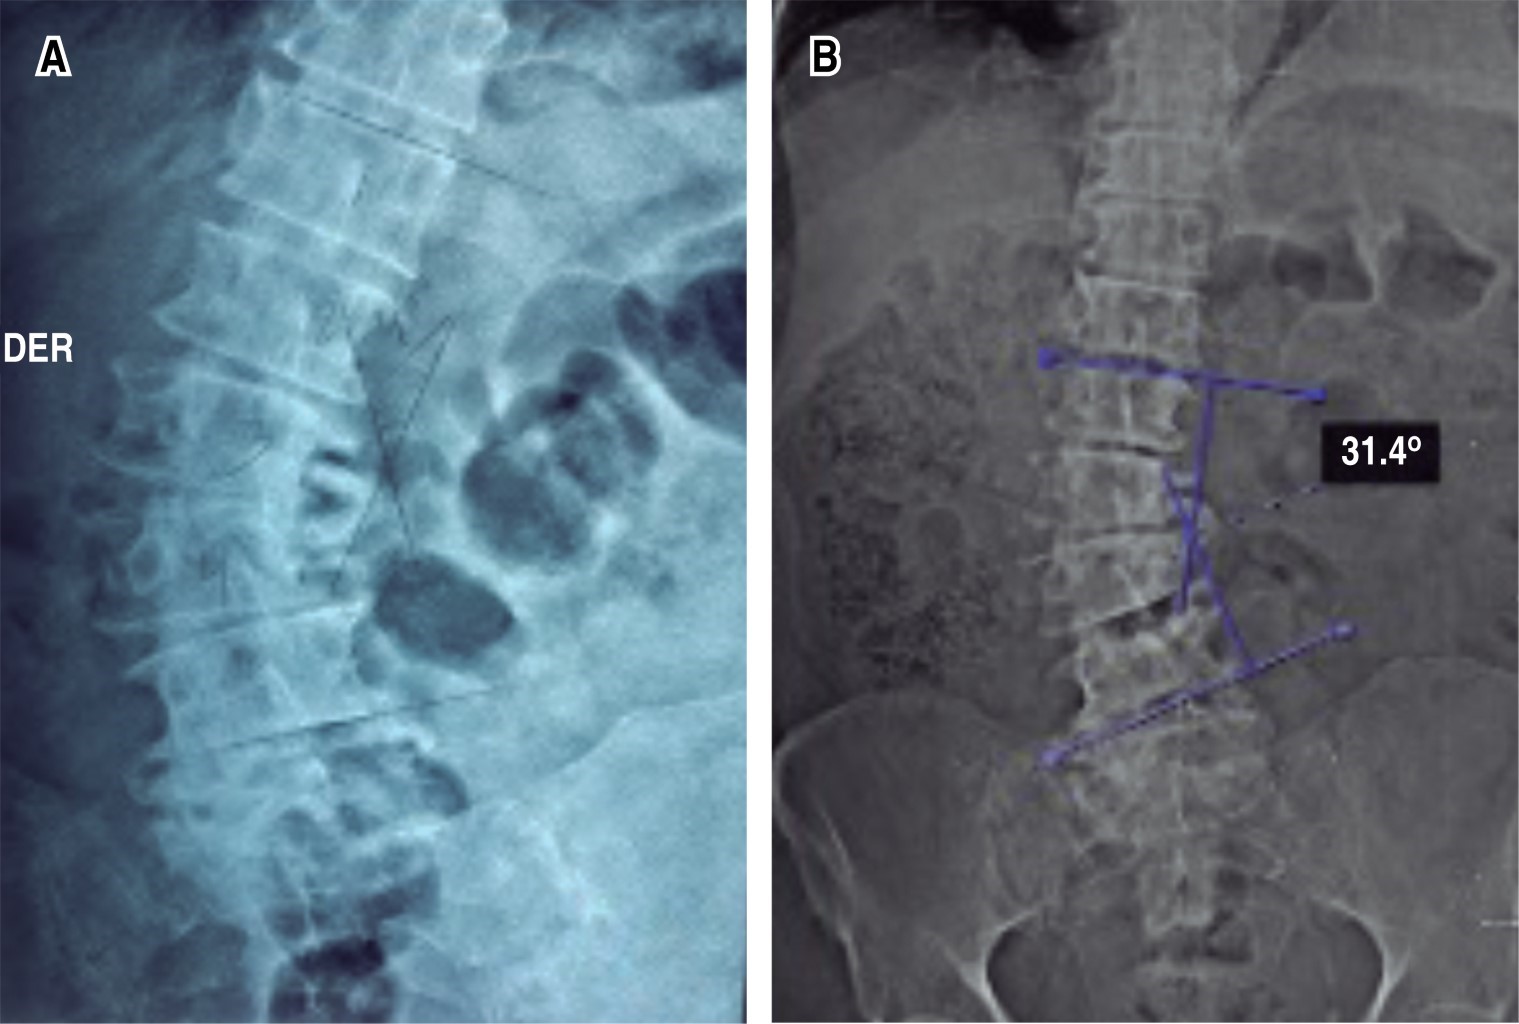

Paciente masculino con escoliosis lumbar degenerativa acompañado de enfermedad de Parkinson (EP). Se instrumenta únicamente los niveles necesarios para corrección de la deformidad coronal, como descompresión de los niveles con estenosis. A pesar de un control radiológico inmediato satisfactorio, en los días posteriores el paciente se aqueja de dolor a nivel de la columna torácica. Rayos X de seguimiento evidencian fractura de la vértebra más cefálica instrumentada. Debido a múltiples comorbilidades, se decide manejo conservador, esperando consolidación del segmento lesionado. Sin embargo, a pesar del tratamiento médico, es llevado cinco meses postoperatorio a sala de operaciones para prolongación de la instrumentación, realizando una transición de una fijación rígida a una semirrígida. El objetivo de la publicación es poner en contexto acerca de la dificultad que conlleva el manejo de un paciente que padezca EP combinado con algún padecimiento degenerativo de la columna.REFERENCIAS (EN ESTE ARTÍCULO)